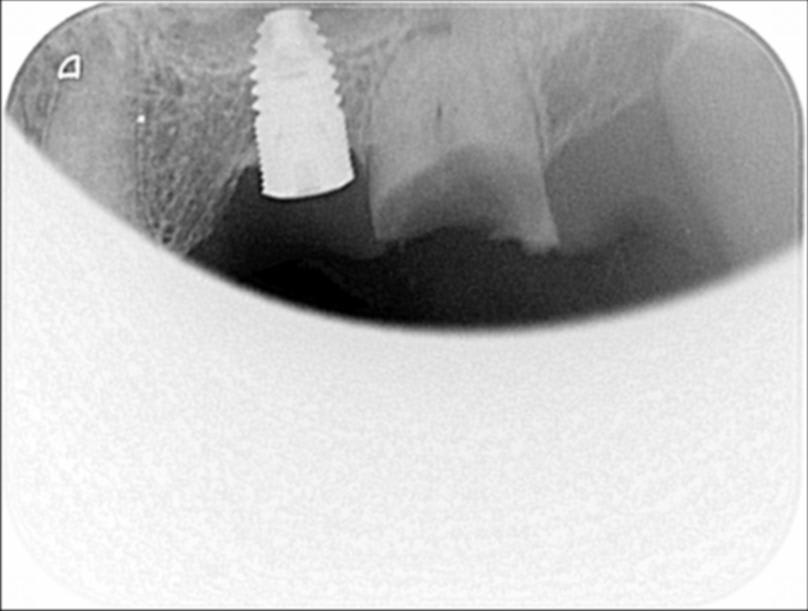

Patient 1 :

Mandibule prothèse sur amovible fixé sur locator (dentiste décédé qui a eu à poser des icx en fin de carriere)

Radio 1, tout au bassinet